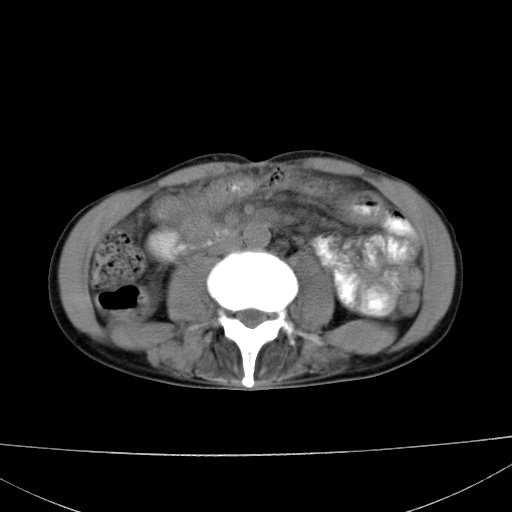

患者 男  41岁,右上腹痛伴腹泻10天,8年前有乙肝,本次b超查肝右叶占位来做ct ,请会诊!

肝硬化\\脾大\\门静脉高压,胃底静脉曲张可能性大.肝右叶肝癌肝内转移,建议增强.左侧小结石.

肝右叶肝癌肝内转移,建议增强

支持肝癌伴肝内转移,脾大,门静脉高压,胃底静脉曲张。

1)考虑肝癌;建议行ct增强扫描检查。2)脾大,门静脉高压,胃底静脉曲张。3)左肾小结石。

1)考虑肝癌及门脉瘤栓,建议行ct增强扫描检查。2)脾大,门静脉高压,胃底静脉曲张。3)左肾小结石。

结合病史;考虑肝癌。门静脉高压,脾大。胃底静脉曲张。

1)考虑肝癌;2)脾大,门静脉高压,胃底静脉曲张。3)左肾小结石。建议行ct增强扫描检查。